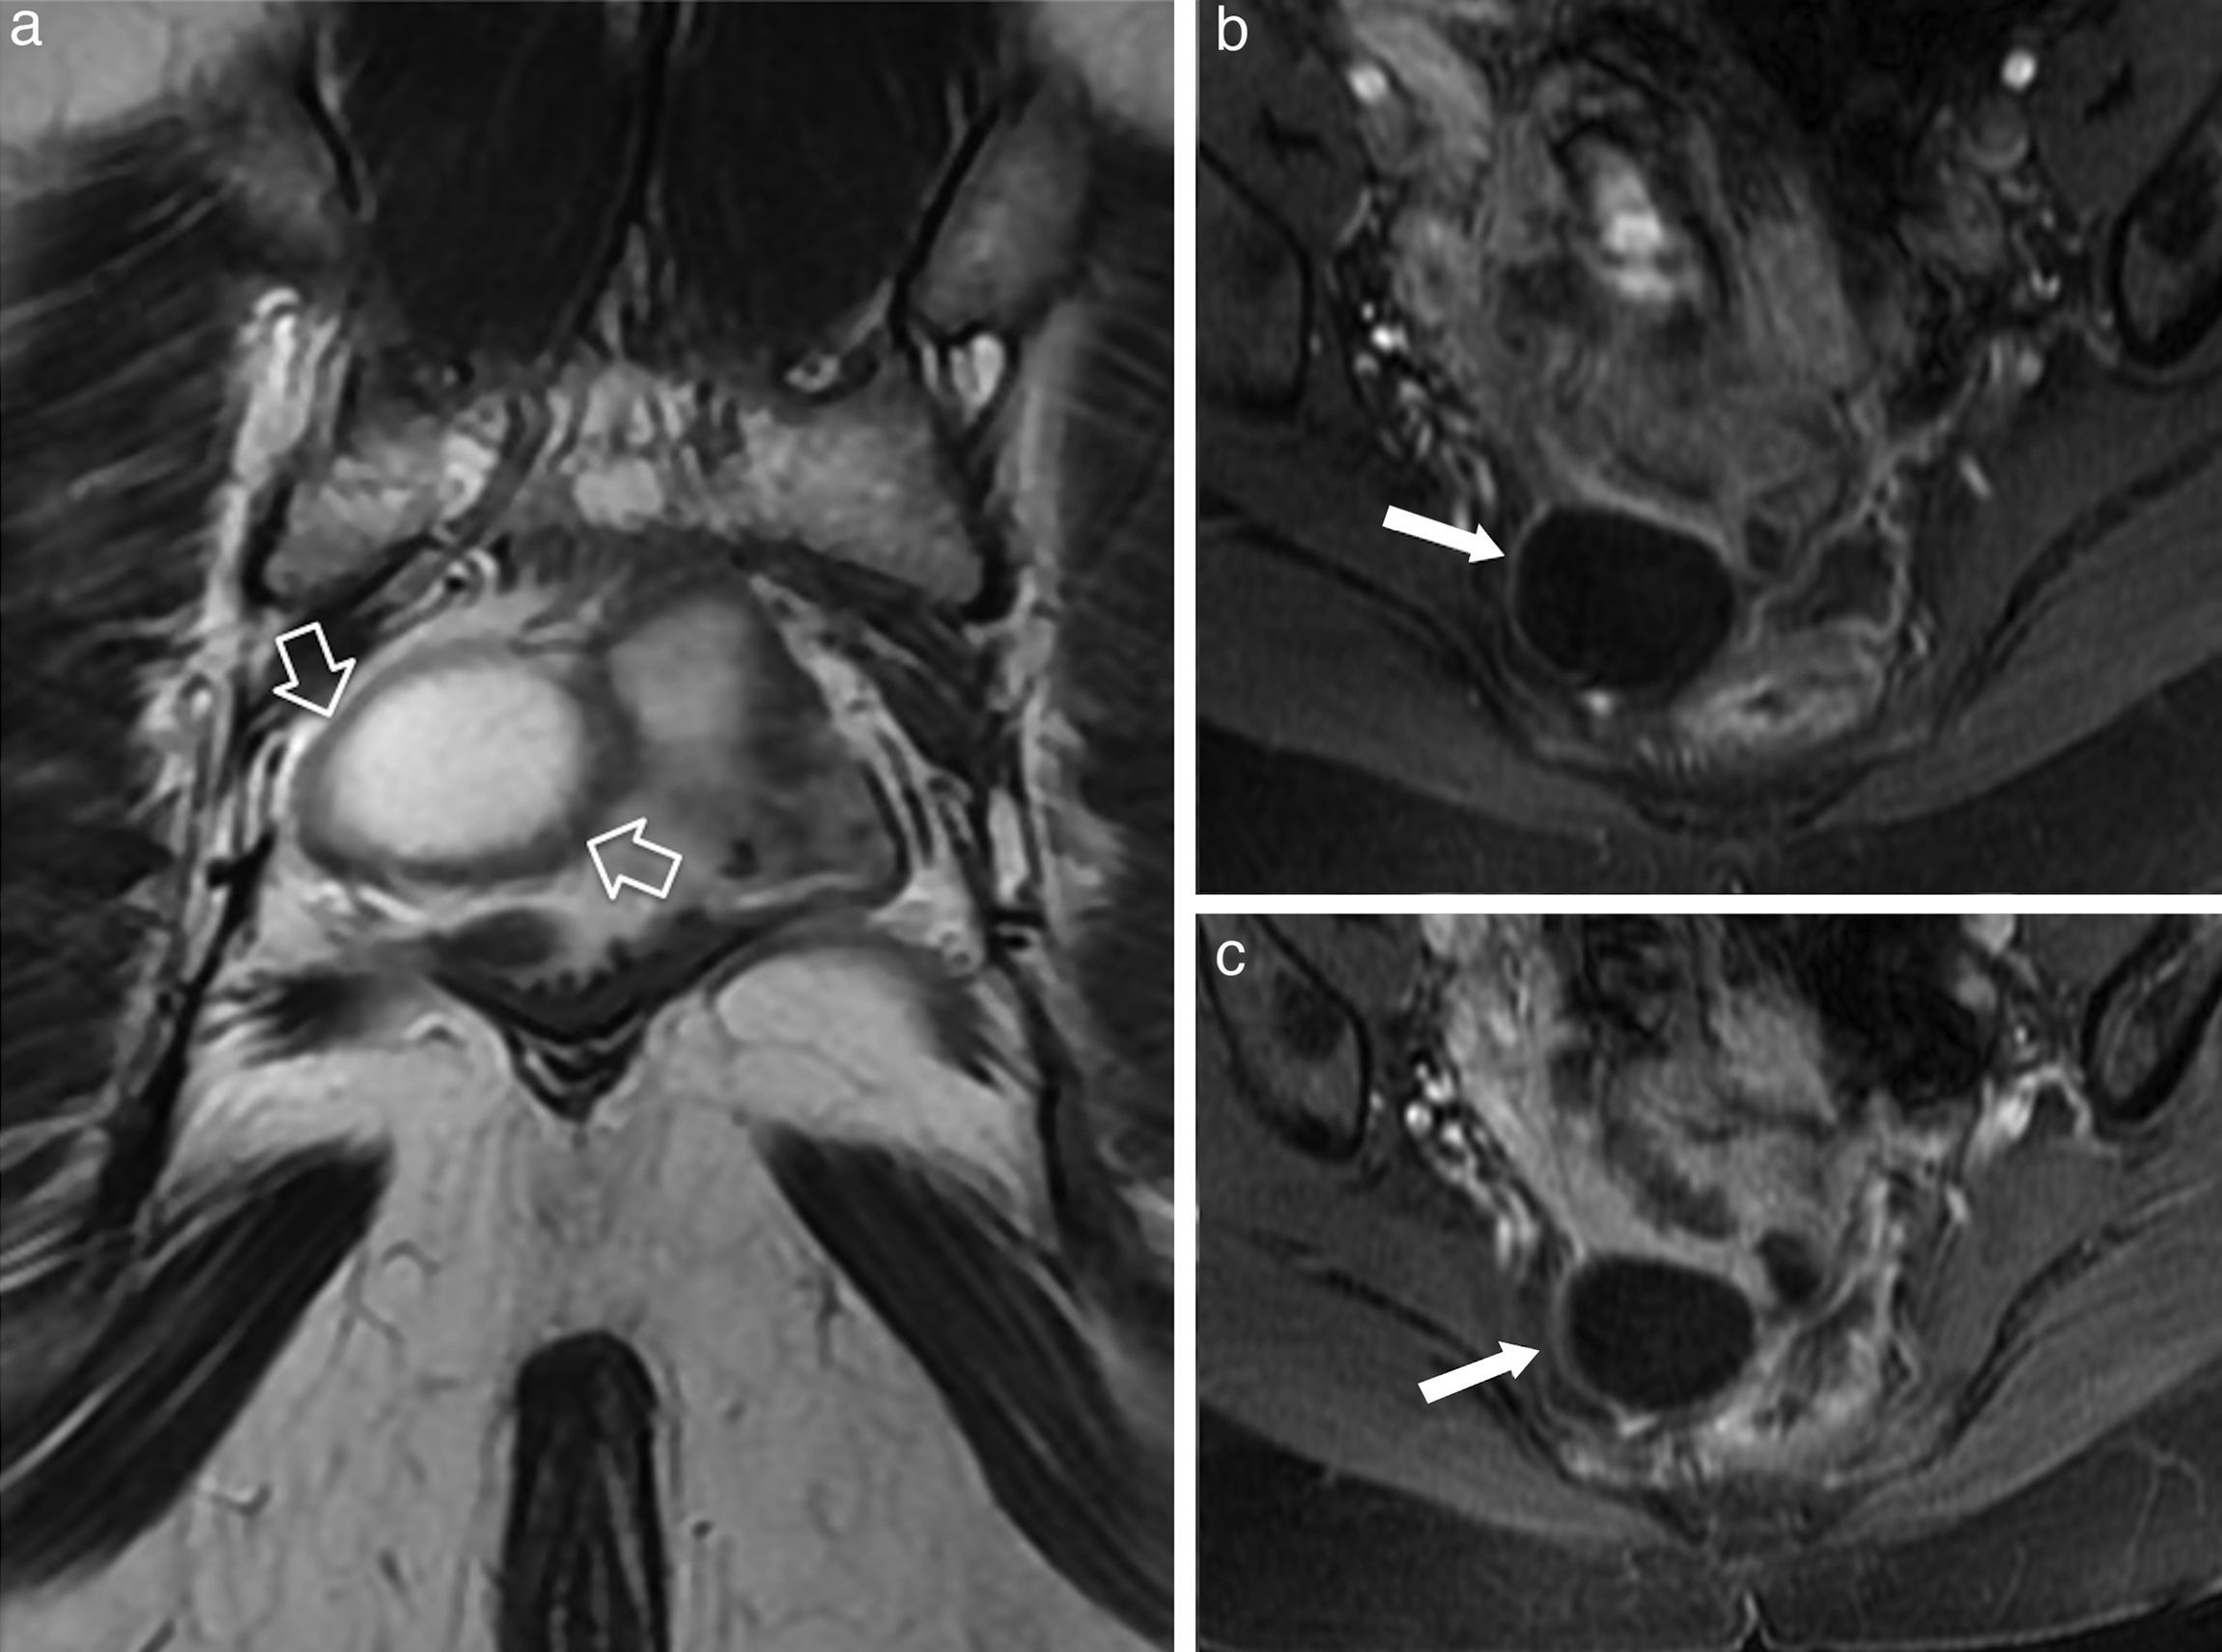

Benign anorectal disease comprises a broad group of processes with very diverse origins; these processes may be congenital or acquired as well as inflammatory or tumor related. However, benign anorectal disease has received less attention in the scientific literature than malignant disease. We present an image-based review of the most common benign diseases of the anus and rectum. In this first part, we review the anatomy of the region and provide a brief description of the peculiarities of the high resolution protocol that we use with 3.0 T MRI. We go on to describe the most common benign anorectal tumors and developmental cystic lesions, together with their differential diagnoses, as well as congenital and acquired anomalies of the anorectal sphincter complex.